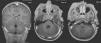

Presentamos el caso de una paciente de 3 años, remitida desde otro hospital por un cuadro de otitis media aguda bilateral, tratada inicialmente con antibióticos orales (amoxicilina-clavulánico en dosis de 50mg/kg/d). Tres días después del inicio del cuadro, la paciente presenta un episodio de cefalea intensa con vómitos y signos inflamatorios retroauriculares izquierdo, por lo que ingresó en este centro. En las pruebas de imagen realizadas se describe en la tomografía computarizada (TC) craneal realizado el primer día de ingreso un absceso de partes blandas retroauricular izquierdo, ausencia de aireación de las celdas mastoideas ipsolaterales (mastoiditis) y un absceso intracraneal, en la fosa posterior, epidural adyacente a las lesiones previas descritas (fig. 1). Por esto, el servicio de Otorrinolaringología decide realizar una timpanocentesis bilateral, evacuación de la mastoides ipsolateral e iniciar un tratamiento antibiótico empírico intravenoso con metronidazol (30mg/kg/d) y cefotaxima (200mg/kg/d). En la resonancia magnética (RM) cerebral y en la angio-RM cerebral, realizada el quinto día, se observa una colección epidural retromastoidea izquierda, con realce periférico, indicativa de absceso epidural, que oblitera el seno transversosigmoideo ipsolateral (fig. 1).

Pruebas de neuroimagen prequirúrgicas. En la imagen de la izquierda: corte axial de la tomografía computarizada craneal con contraste, en la que se observa un absceso retroauricular izquierdo de partes blandas, un absceso epidural en fosa posterior y las celdas mastoideas no aireadas ipsolaterales. En la imagen central: secuencia de la angiorresonancia magnética, el seno transversosigmoideo izquierdo no presenta flujo. Prueba de neuroimagen posquirúrgica precoz. En la imagen derecha: corte axial donde se observa la recanalización parcial del seno tras la evacuación el absceso.

En la TC craneal de control realizada a las 24h de la cirugía se observa una recanalización parcial de esta, con un aumento del retorno venoso ipsolateral a través de la vena de Dandy o petrosa inferior y del seno petroso superior (fig. 1), por lo que se decide no comenzar con la anticoagulación.